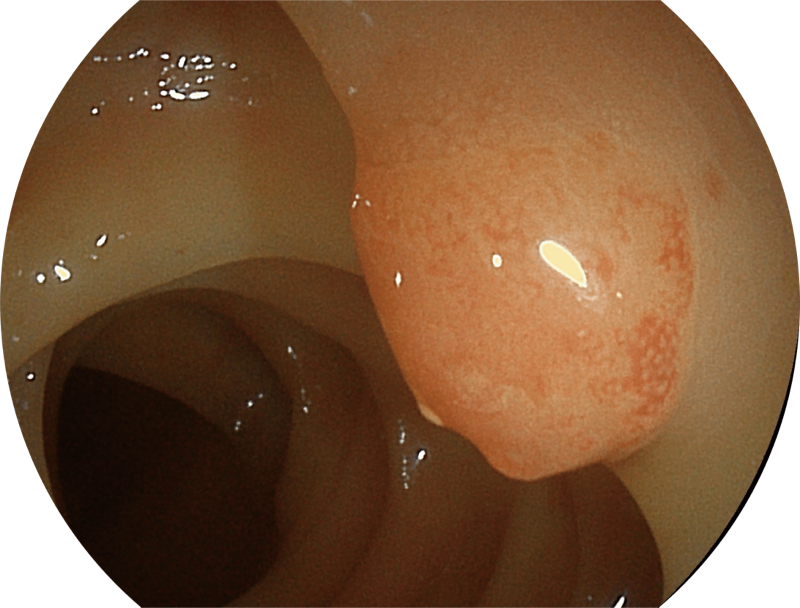

百万级像素高清传感器,1080P全高清视频信号输出,图像清晰。

图像具有高亮度、高黏膜血管颜色对比度的特点,且不改变粘液、食物残渣、粪便的基本颜色,可在中远景下进行观察,助力消化道早期疾病的诊断。